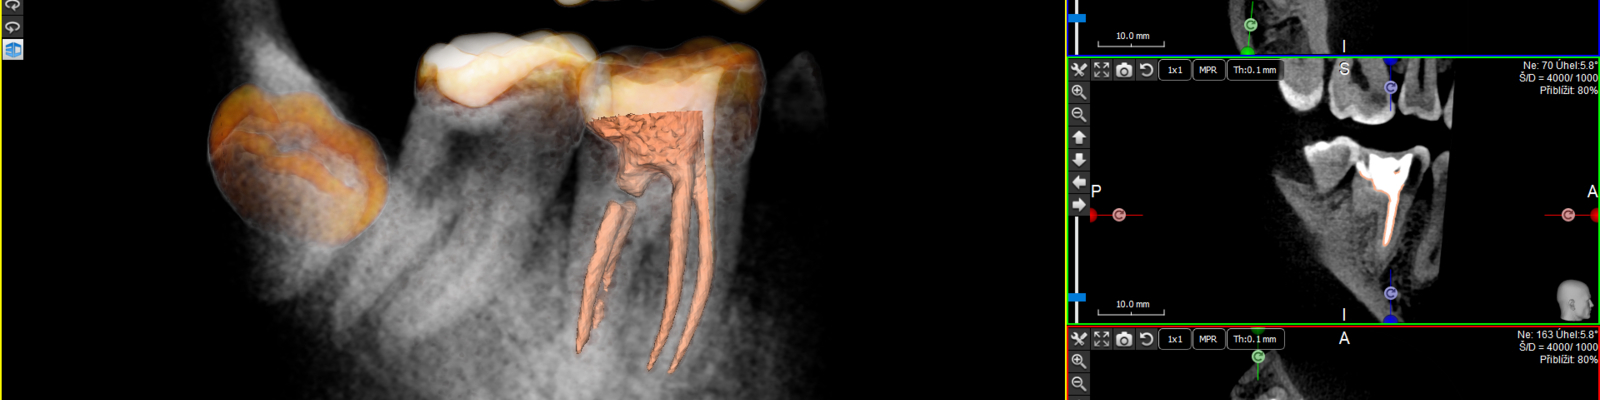

3D CBCT zobrazení pro endodoncii je dostupnější než kdy dříve a nabízí nejen chytré a kompaktní řešení. Diagnostikujte pomocí nejvyšší kvality 2D a 3D snímků. Přístroje X-Mind od ACTEON SATELEC poskytují mimo jiné využití pro dokonalou diagnostiku endodontických případů. Využijete je zejména před reendodoncií, před ošetřením komplikovaných kořenových kanálků atd. Ovládací software je v Českém jazyce, a proto zajistí jednoduché ovládání všem uživatelům vašeho týmu. Pokud máte jakýkoliv dotaz ohledně přístrojů kontaktujte nás buďto skrze kontaktní formulář, telefonicky nebo kontaktujte svého obchodního zástupce. Ovládací software a možnosti využití je možné vyzkoušet a zjistit o nich více, pořádáme kompletní praktické kurzy po celé ČR, termíny a možnost přihlášení najdete v sekci Školení.